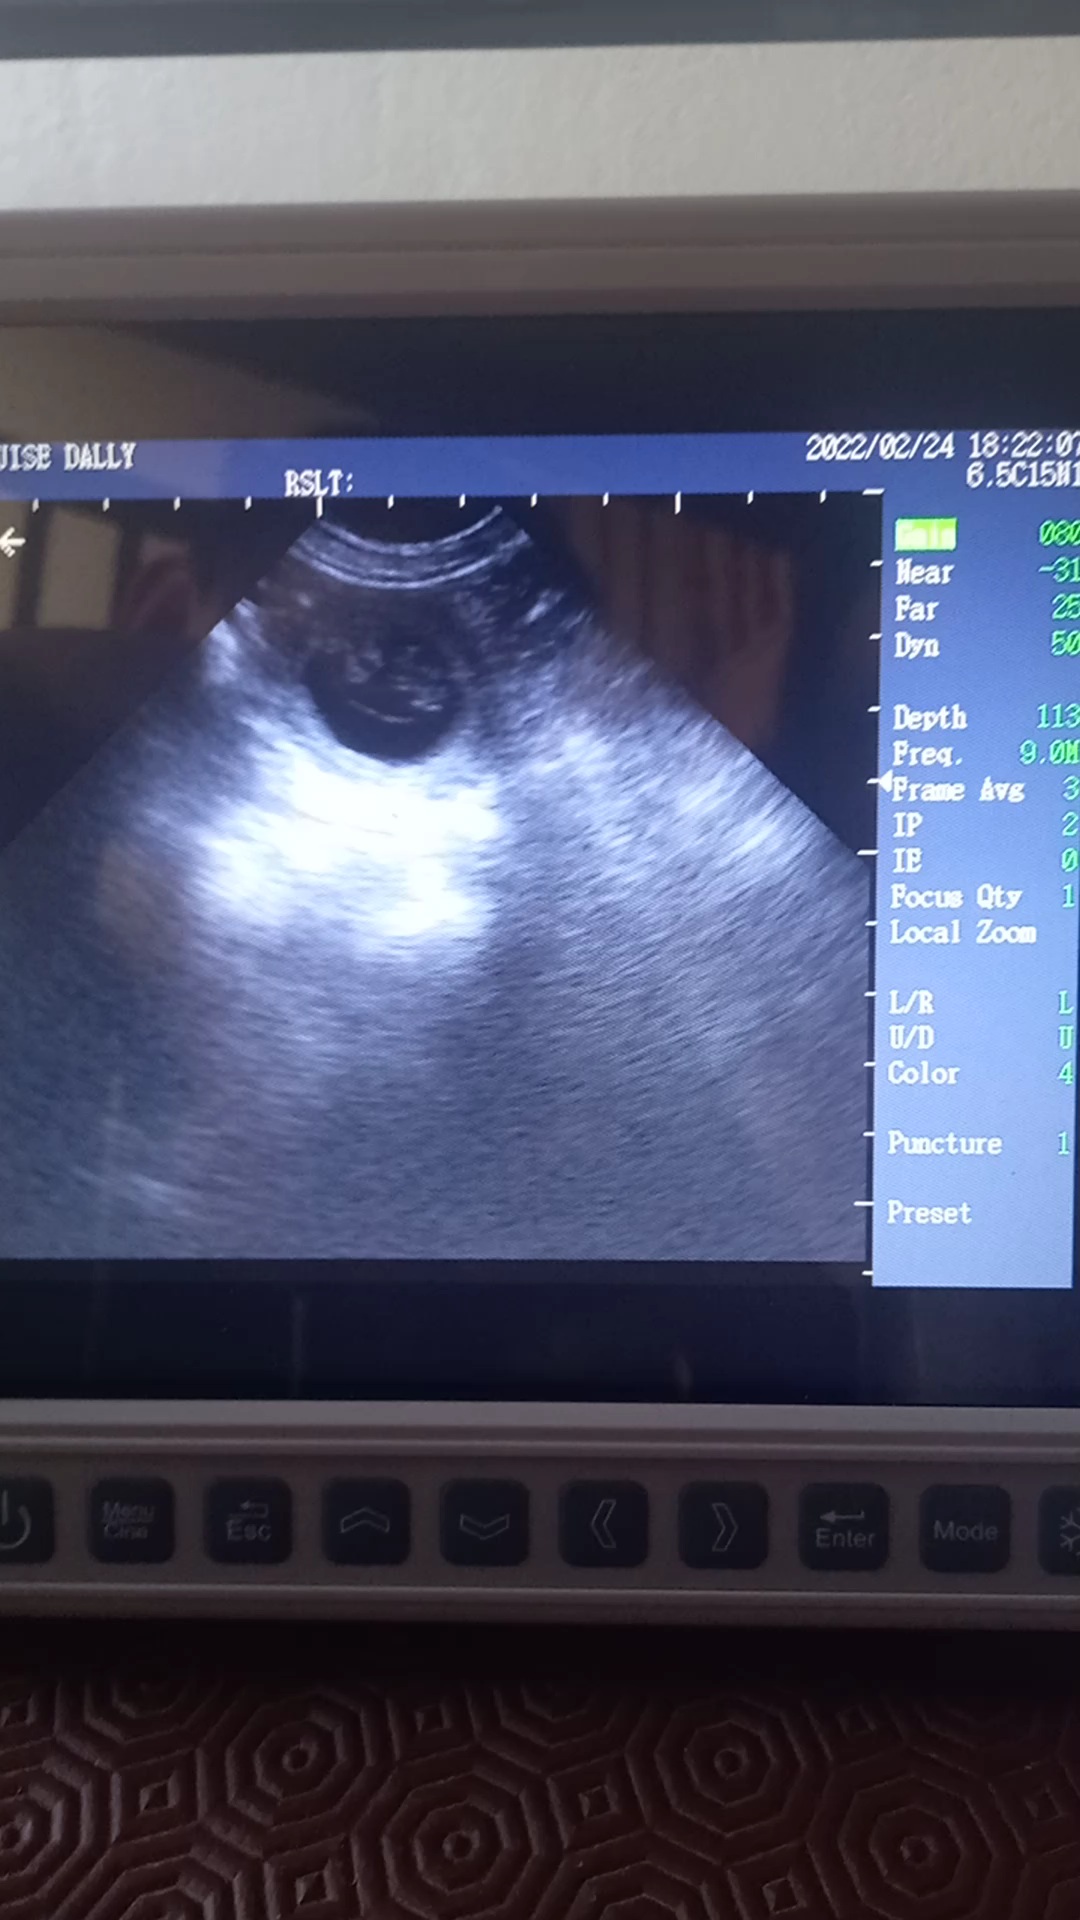

Beautiful scan of a 4yr old Labrador, confirmed multiple pups at 30days.